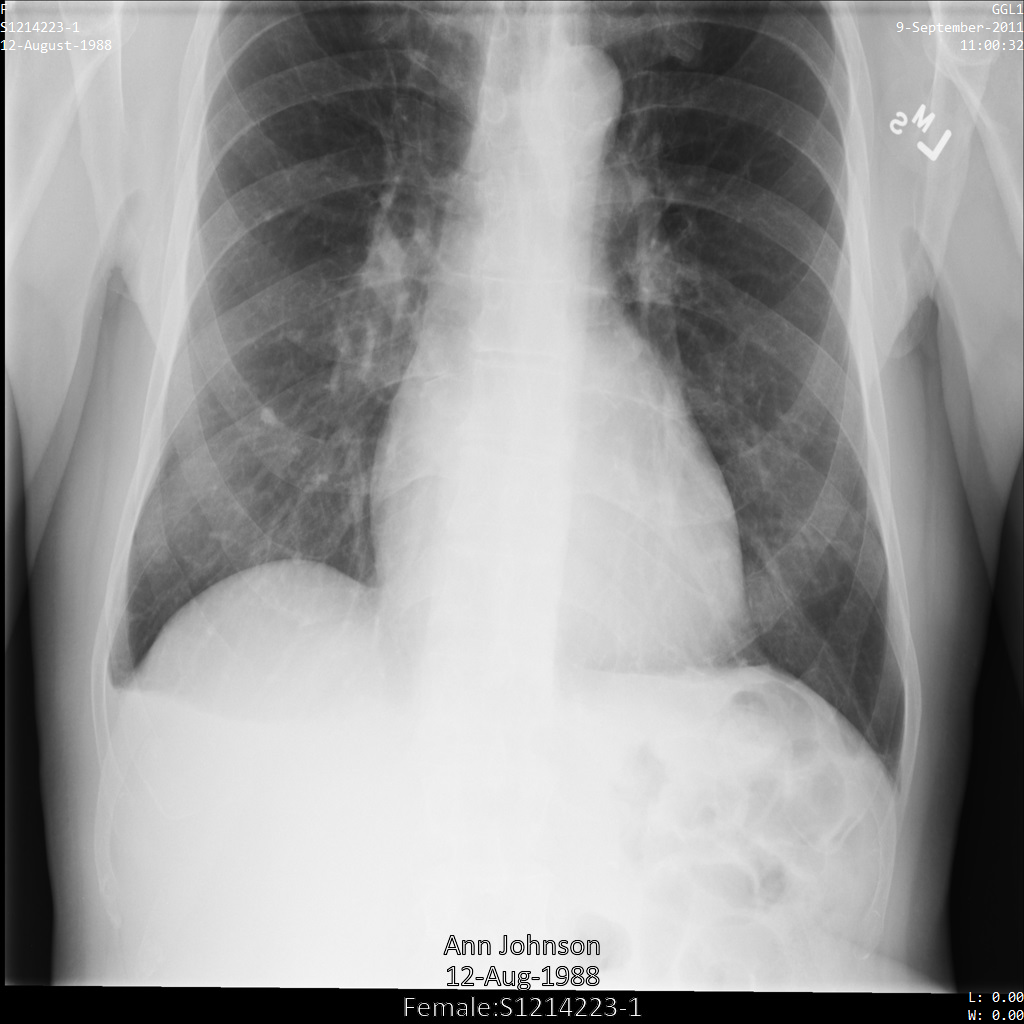

En cada una de las siguientes secciones, se proporcionan ejemplos de cómo desidentificar datos de DICOM mediante varios métodos. Se proporciona un resultado de la imagen desidentificada en cada muestra. En cada muestra, se usa la siguiente imagen original como su entrada:

Puedes comparar la imagen de salida de cada operación de desidentificación con esta imagen original para ver los efectos de la operación.

Después de enviar la imagen a la API de Cloud Healthcare, la imagen aparece de la siguiente manera. Mientras se ocultan los metadatos que se muestran en las esquinas superiores de la imagen, la información de salud protegida (PHI) quemado en la parte inferior de la imagen permanece. Para quitar también el texto quemado, consulta Oculta el texto quemado de las imágenes.